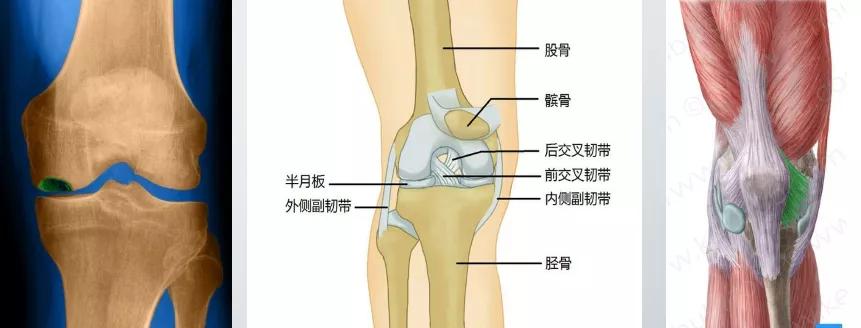

而膝关节几乎就是两个平面贴在一起

单靠骨头几乎没有稳定性

其稳定性全靠关节内外的韧带和肌肉

韧带,除非损伤,其稳定作用一般变化不大

人和人之间最容易出现差别的是 肌肉力量

肌肉力量差的人,膝关节稳定性就差